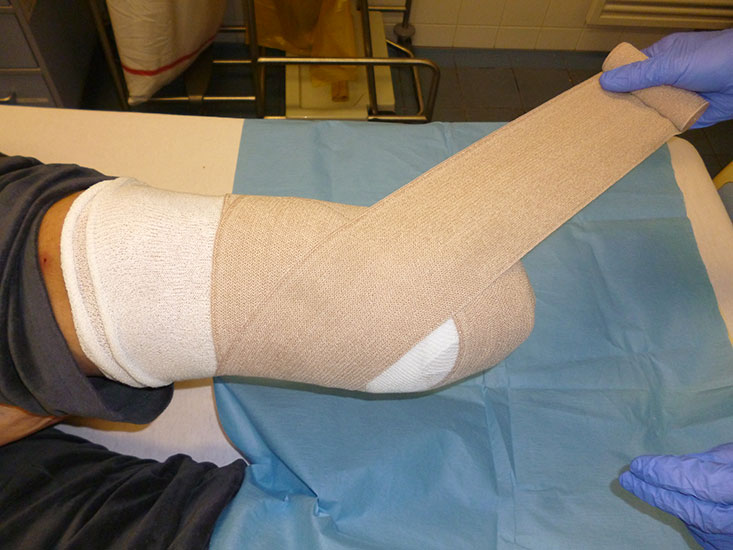

Zu achten ist auf einen gut sitzenden elastischen Kompressionsverband, der bei einer PAVK nur vorsichtig angezogen werden darf. Dieser soll einerseits zur Verhinderung der Nachblutung und andererseits zur Stumpfkonfiguration beitragen (Abb. 77). Die Ruhigstellung in einem Cast begünstigt die Wundheilung.